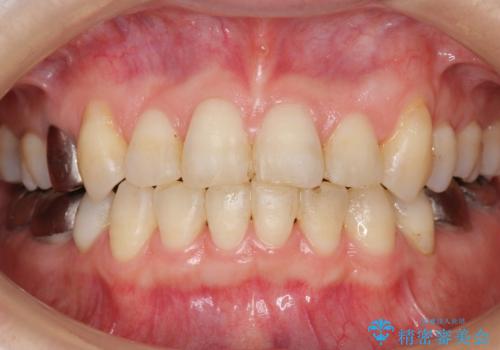

低予算で銀歯を白くしたい 50代女性

- 低予算で銀歯を白くしたいとご希望し来院された患者様です。

銀歯がなくなったとことで口元の印象が明るくなり、ご満足頂けました。

「これで大きく口を開けて笑っても大丈夫だわ!」と喜んで下さいました。